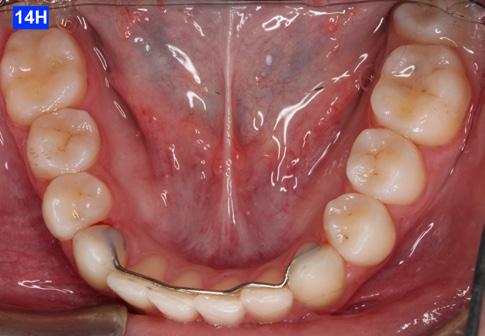

Please view the post-treatment images at the time of insertion of the retainers (Figure 14 - A, B, C. D, E, F, G, H, I, J, K, L, M, N).9

Figure 14H: Post-treatment, mandible, occlusal view